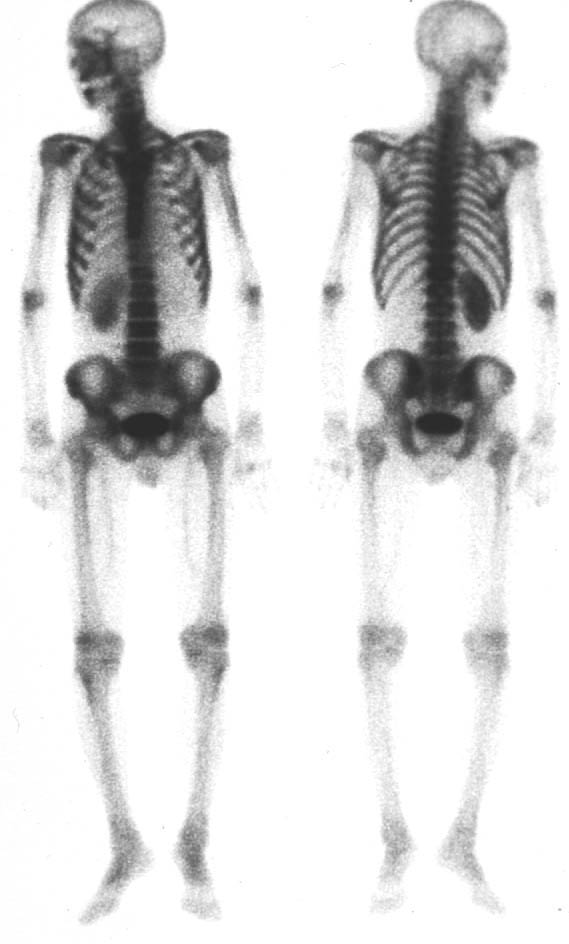

| 第196回定例研究会(1997.6) 骨シンチ『異常集積の少ない骨転移』 | 神奈川県立がんセンター | 小野 慈 |

(2)compartment解析に関しては代表的なものは、1-compartment model(秀毛らの非線形model(Fig.3)に始まるが、篠原が報告した如く線形modelでの短時間に演算可能な方法でも実用的であった。Veraらが唱えた3-compartment modelは採血を伴うmodel式を利用しており、やや煩雑さを伴っている。河らが提唱した5-compartment modelは複雑な計算式を必要としているが、肝最大除去率(Rmax)を算出可能である。(Fig.4)病的 hotなし。 | 第12胸椎に骨溶解像。 | 第12胸椎に 低信号域。 |

![]() | ![]() | ![]() |